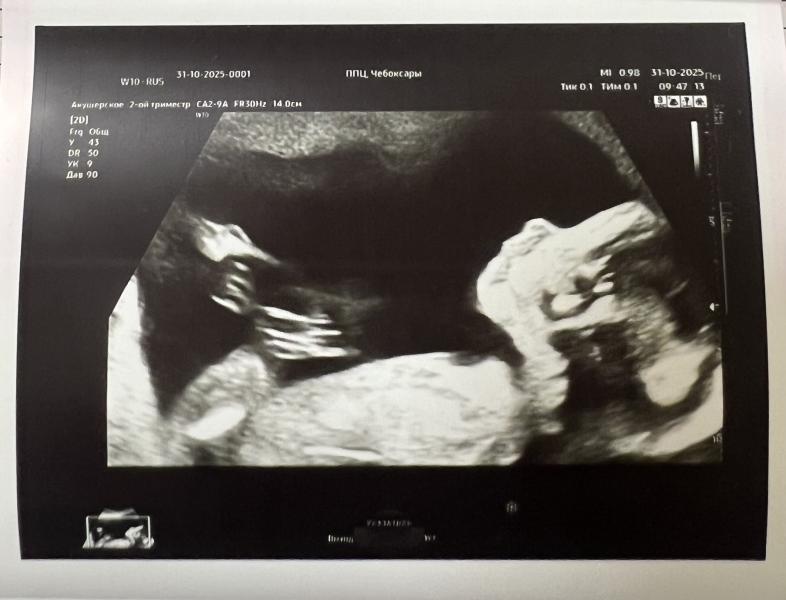

20 недель . 2 скрининг пройден . По узи все хорошо. Есть хлопьях в водах после ковида . Но они никуда не денутся до родов .